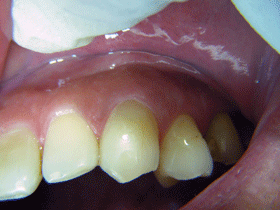

一度も虫歯になってない口腔内

症 例